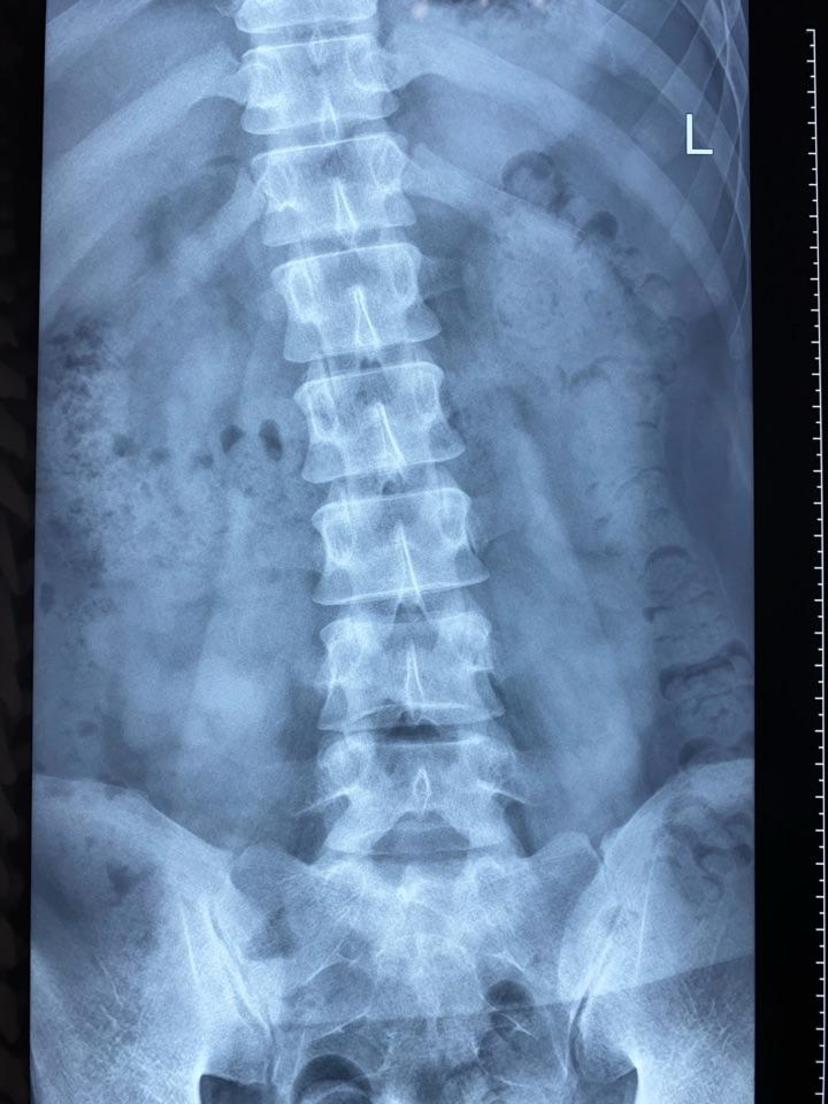

术前X线显示脊柱侧弯严重

术前站不直,呈S型侧弯

短节段术后X片显示:脊柱完全直了